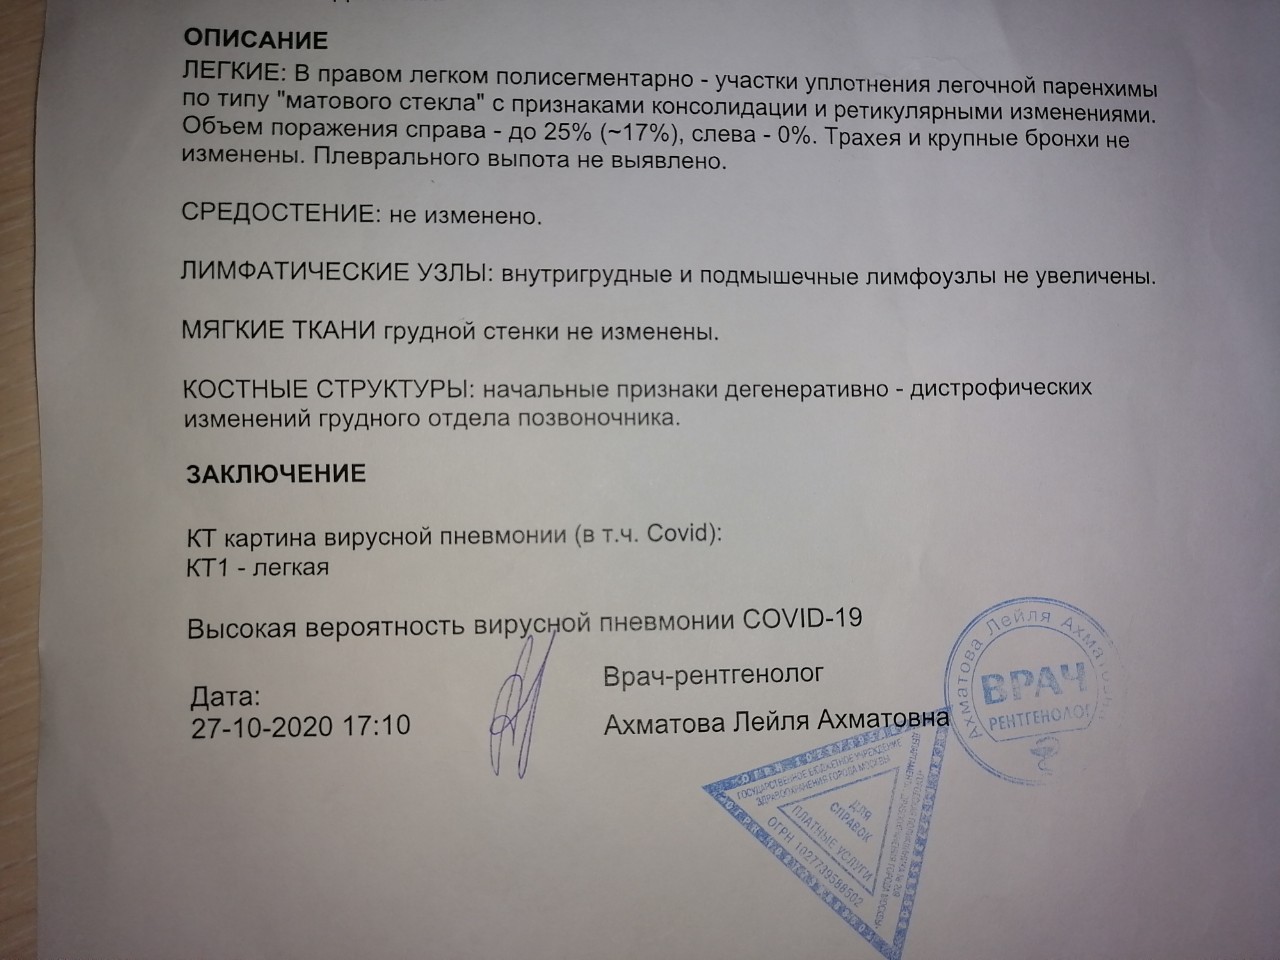

Острая внебольничная пневмония по МКБ-10: признаки и примеры